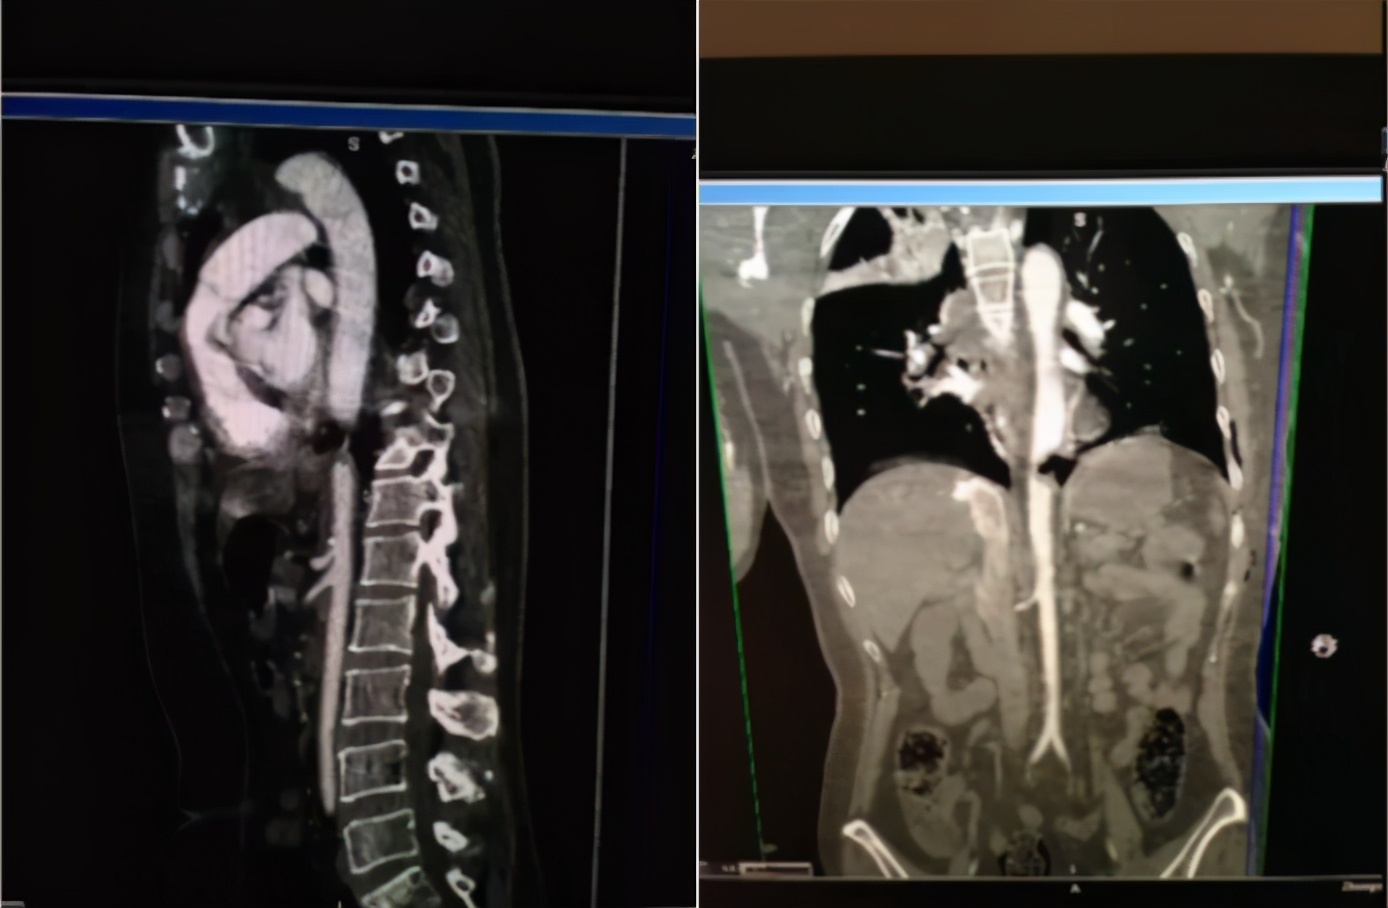

在PACU中进行全面的体格检查,发现患者双侧股动脉、腘动脉和足背动脉未扪及,双下肢苍白,皮温降低。联系CT室行胸腹主动脉CTA,CT扫描结果显示胸主动脉下段狭窄。

8.立刻剖胸探查,真相大白

再次手术记录:患者麻醉后,常规消毒铺巾。沿原切口打开皮肤、皮下组织、肌肉,后断第六肋,进入胸腔。探查:左侧胸腔少量血性积液。予冲洗创面,见原滋养血管Hem-o-lock夹闭处主动脉部分狭窄。在狭窄上下端分别阻断主动脉,小心剪断Hem-o-lock,滋养血管回缩形成降主动脉破口,直径约5 mm,以3-0 prolene线缝合破口,解除阻断(阻断时间约20 min),见主动脉搏动良好,置胸管1根行闭式引流。膈肌以上胸主动脉狭窄+阻断时间约为7.5 h。